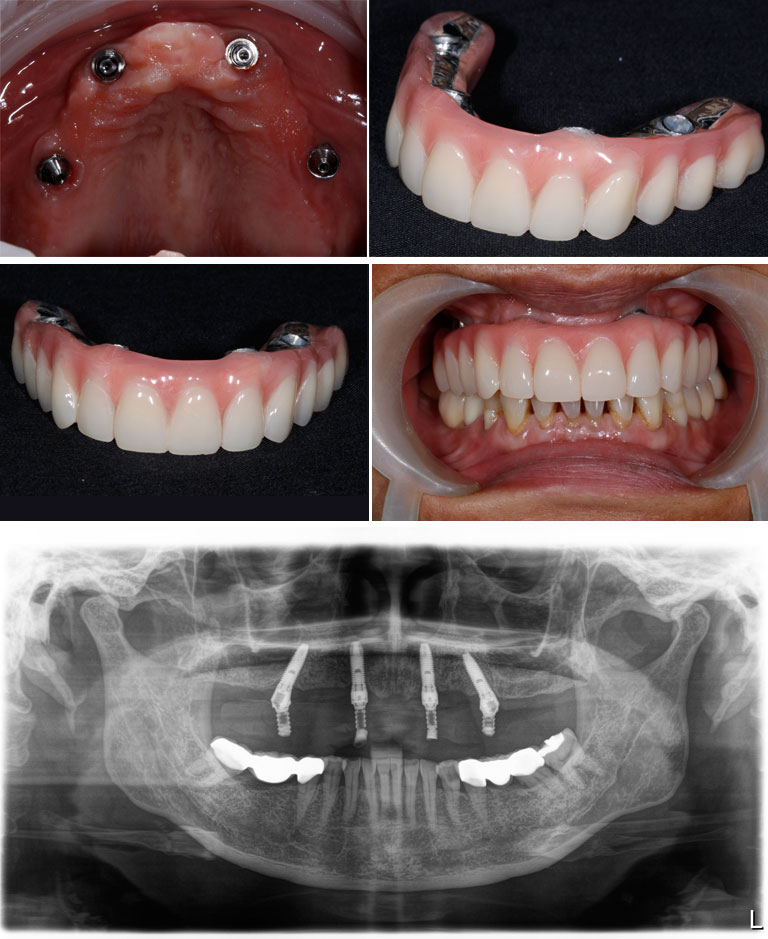

All-on-4 techniques allow us to deliver immediate teeth with the FIXED provisional prostheses. Later on, after 4 – 6 months, the final prosthesis will be delivered.

We utilize advanced imaging techniques, including OPG x-rays and CT scans, to ensure precise implant placement and optimal results.

1st Trip : You will get your FIXED provisional prostheses.

2nd Trip : You will get your final prostheses .Fixed Prostheses OR Removable Prostheses.